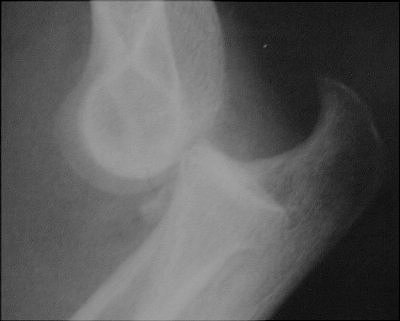

Return to Coronoid Process Fracture